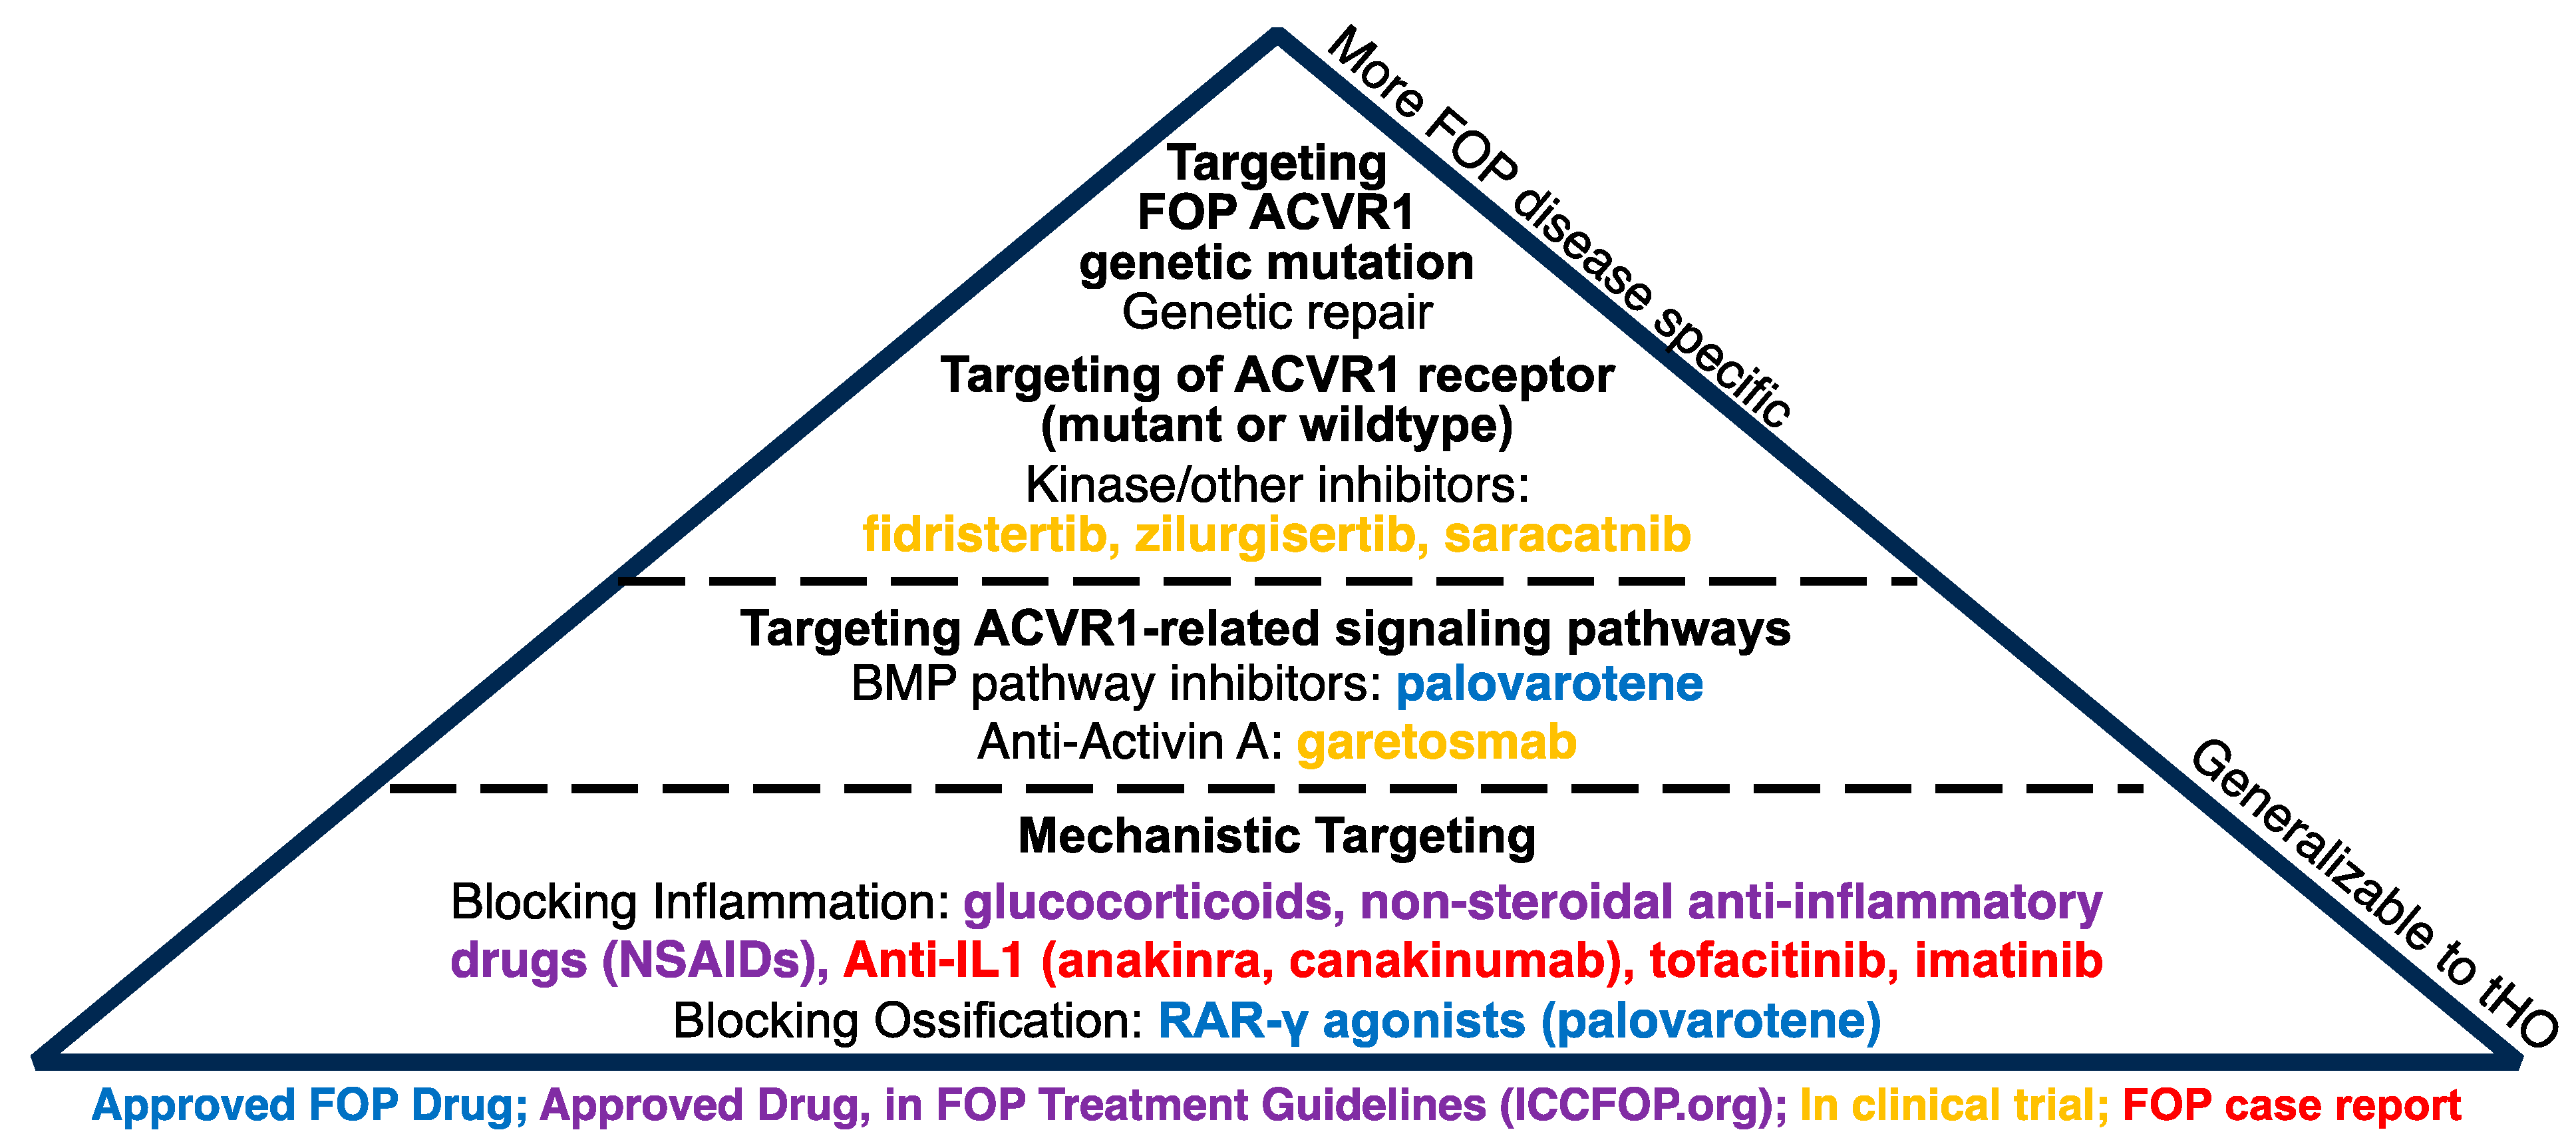

8.2. Genetic HO

9. Conclusions